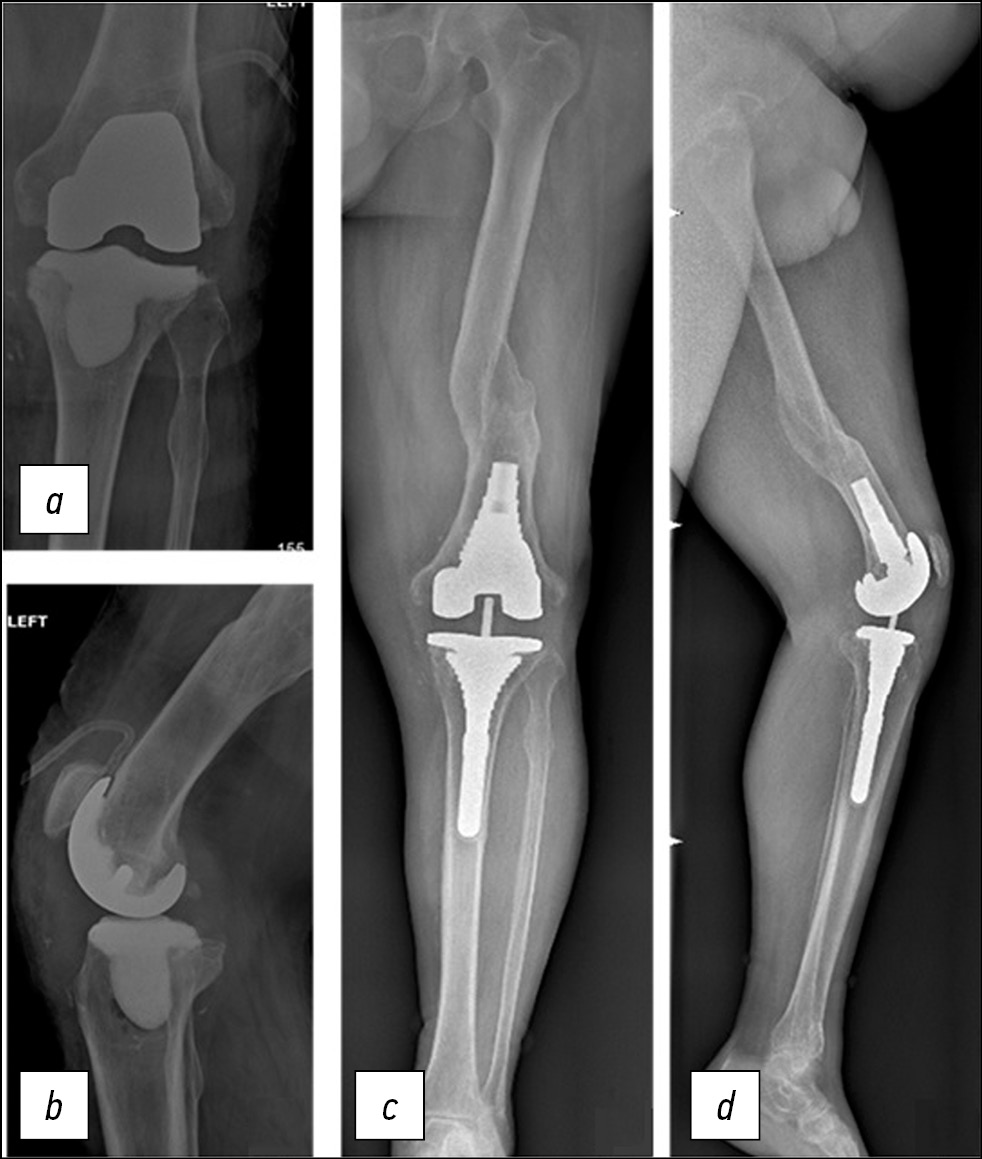

Необходимо отметить, что периодически встречаются пациенты с обширными костными дефектами типа IIb и III по классификации AORI, у которых не удаётся достигнуть стабильной фиксации метафизарной втулки. Так, при лечении пациента М., возраст 59 лет, с асептической нестабильностью тибиального компонента и сформированным типом костного дефекта F1/T2b по AORI (рис. 4) мы приняли во внимание периферический большой дефект медиального мыщелка и отсутствие ротационной и аксиальной стабильности тестовой втулки (рис. 4, В). Для предотвращения последующего асептического расшатывания компонентов ревизионного эндопротеза в нашем алгоритме предлагается использовать опорные реконструктивные конусы из титана (рис. 4, С). Для установки конуса из трабекулярного металла применяются рашпили или высокоскоростной бур для обработки кости без риска перелома.

Рис. 4. Рентгенограммы больного М., 59 лет. Дефект типа F1/T2В по AORI (a). Учитывая обширный костный дефект, добиться стабильности метафизарной втулки не удалось (b). Принято решение перейти на метафизарный конус (c).

Fig. 4. X-ray images the 59 y. o. patient M with F1/T2B AORI defect (a). The metaphyseal sleeve failed due to the extensive bone defect (b). The decision about switching to a metaphyseal cone was made (c).

В случае, когда необходимо выполнить дистально расширенный доступ к коленному суставу с остеотомией бугристости большеберцовой кости, предпочтительным будет использование конусов из трабекулярного металла. Это обусловлено возможностью рефиксации бугристости к конусу из трабекулярного металла с помощью винтов и проволочных трансоссальных швов.